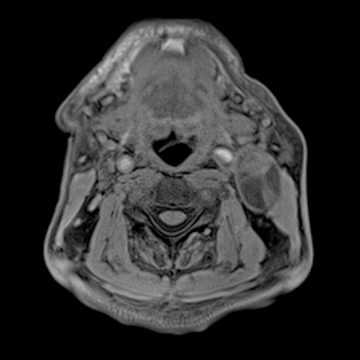

頚部腫瘍

- 造影3D VIBE

- 体動の影響を受けにくい